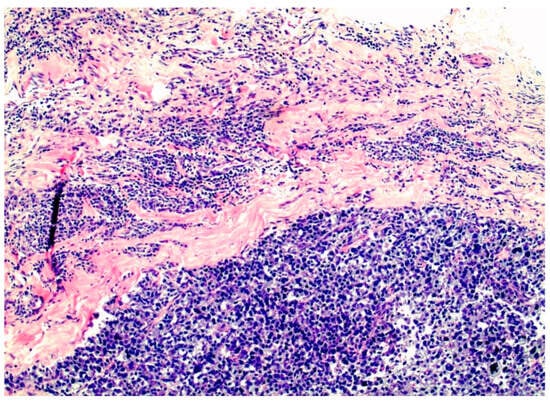

Figure 5.

Triple-negative, basal-like breast cancer filling the interstitial spaces between the pink collagen bundles of the interstitium.